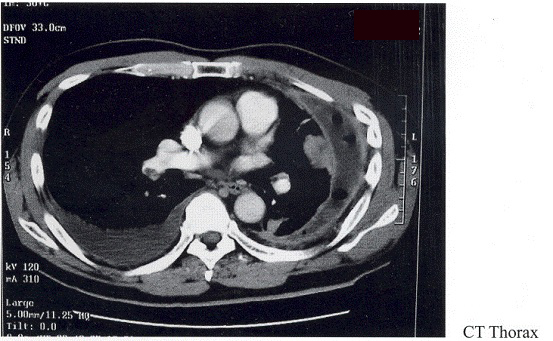

Software: Microsoft Office

CT thorax in HKSH showed large loculated left pleural effuion with thickened pleura, trace right pleural effusion, a mass in lingual lobe, decrease size of left chest and a filling defect in right pulmonary artery compatible with right pulmonary embolism. He was put on low molecular weight heparin (LMWH) then. CT guided lung biopsy showed organizing pneumonia with no malignancy. The left lung failed to expand despite pleural fluid drainage afterwards. Screening for hypercoagulability including antithrombin III, protein C, protein S, lupus anticoagulant and phospholipid antibody were all negative. He was discharge home on 30th August, 2001 with LMWH.

Echocardiogram repeated on the day of arrival to our hospital showed normal size right and left ventricule with normal systolic function, no feature of acute right heart strain and a small rim of pericardial effusion. CT

thorax repeated on 28thSeptember showed similar finding as previous CT thorax except no evidence of embolism in the main pulmonary arteries. LMWH was restarted. Surgeon was consulted and thoracoscopic lung biopsy was performed on 9thOctober. Intraoperatively, very thickened and fibrotic pleura present throughout the whole left chest with encasement and collapse of the left lung. Decortication was not performed since it was considered very difficult due to chronicity and amount of fibrosis, as well as the possibility of malignant disease.